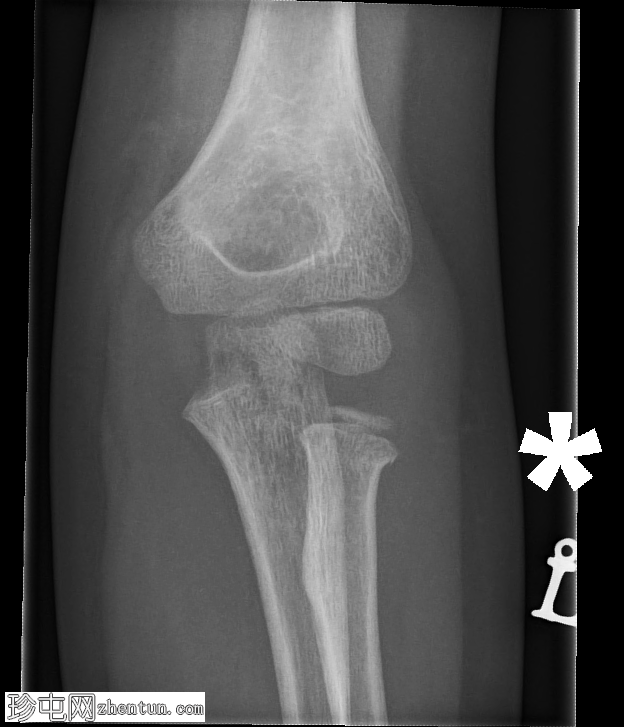

正位片

可见鹰嘴关节内骨折,桡骨颈轻度移位骨折,侧位片可见轻微硬化。肘关节对位良好。关节积液,表现为前后脂肪垫抬高。

儿科,桡骨颈骨折比桡骨头骨折更常见(与成人相反)。如本例所示,桡骨颈骨折通常表现隐匿,轻微硬化或轻度成角可能是唯一的体征。

务必始终评估关节对位情况。如果存在桡骨小头关节脱位,则该损伤属于蒙特吉亚骨折脱位。描述关节对位正常非常重要。